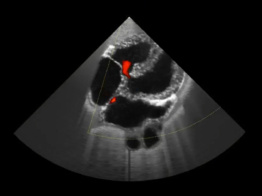

HeartWorks

A globally recognized cardiac learning platform, with simulation in cardiac anatomy, transthoracic, transesophageal echocardiography (TTE/TEE) and live 3D echocardiography. Ideal for programs prioritizing realistic cardiac anatomy and pathology.

Real Ultrasound Data

TTE, TEE & Live 3D Echo

• Over 100 patient cases with broad range of pathology

• Practice with pathology-rich, clinically realistic scenarios